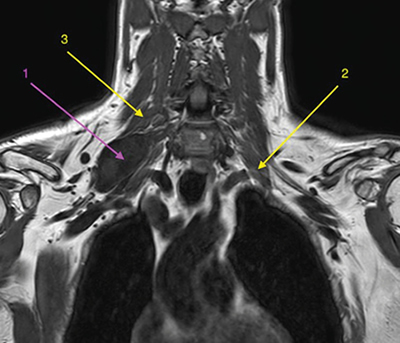

Con la orientación diagnóstica inicial de schwannoma de plexo braquial derecho con escasa repercusión clínica, se decidió actitud expectante. Se instauró tratamiento analgésico de primer escalón y ansiólisis a demanda para dormir. El paciente era reticente al tratamiento neuromodulador debido a sus efectos secundarios. Seis meses después, tras una nueva RM de control, se observó un discreto crecimiento de la lesión con probable efecto compresivo por los músculos escalenos anterior y medio (Figuras 1 y 2). Se indicó una infiltración diagnóstico-terapéutica con toxina botulínica tipo A (Botox®) ecodirigida. Las crisis de dolor eran más frecuentes y de más minutos de duración y empezaban a afectar su calidad de vida. EVA 2-3 en reposo, 8-9/10 en las crisis.

Fig. 1. RM coronal en T1. 1. Schwannoma de plexo braquial derecho. 2. Músculo escaleno anterior izquierdo, para mostrar su ubicación relativa al plexo braquial ipsilateral, dado que en el lado derecho no se identifica claramente. 3. Músculo escaleno medio derecho